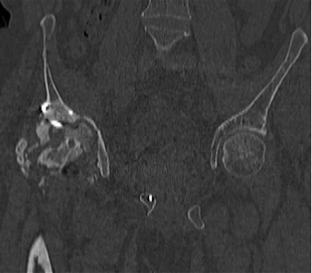

Пациент 49 лет, паровозная травма 23.2.2006, получил вертикальная нестабильное повреждение таза, разрыв левого крестцово-подвздошного сочленения, перелом лонной, седалищной костей слева, T-образный оскольчатый перелом правой вертлужной впадины с переломом заднего края, вывих правого бедра, посттравматическая пояснично-крестцовая плексопатия с обеих сторон, паралич мышц правой голени.

В день травмы - вправление вывиха, скелетное вытяжение, 14.3.2006 чрескостный остеосинтез таза. 20.4.2006 остеосинтез правой вертлужной впадины пластинами, осложнившийся нагноением межмышечной гематомы правой ягодичной области. Получал консервативное лечение, было достигнуто полное заживление раны. 24.7.2006 введены илиосакральные винты слева. С декабря 2006 года и по настоящее время ходит на костылях без опоры на правую ногу. Планируется THA. Помогите определиться с вариантом костной пластики? И какую укрепляющую конструкцию использовать?